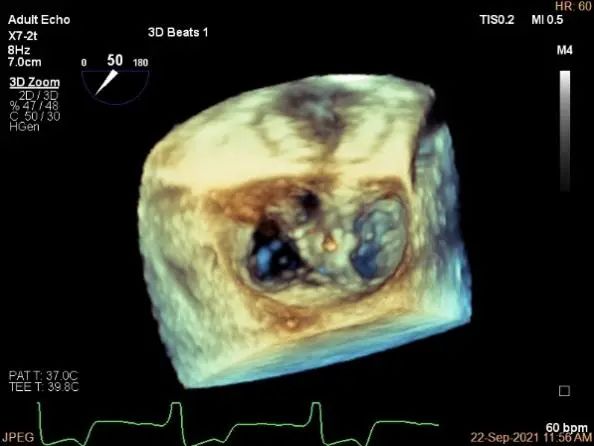

三维评估两个夹子位置

3D-color再次确定未见残余分流

评估瓣口条件,平均跨瓣压差:4mmHg

3d确认夹子位置在P1区

3d-color确认残余分流情况